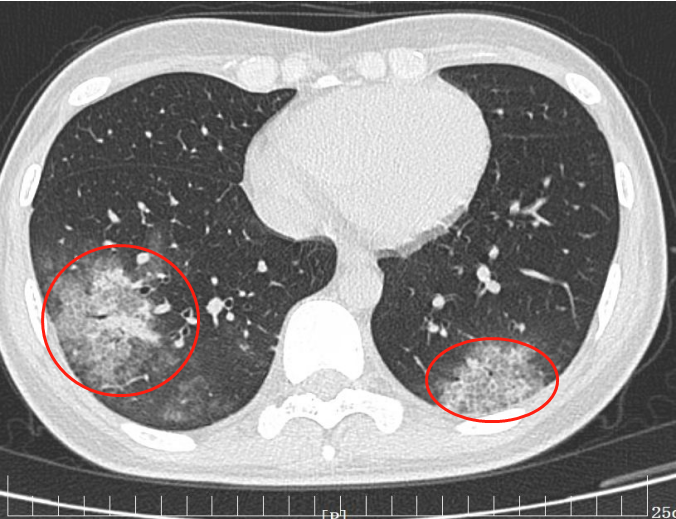

就诊于西安高新医院呼吸与危重症医学科后,行胸部 CT 检查,发现她肺部多发「团片影」。蹊跷的是,李霞医生发现其肺部病灶与普通肺炎影像表现不一,那么,致其不适的感染病原微生物到底是什么?令人匪夷所思。

呼吸与危重症医学科高和飞副主任仔细查阅小杨的胸部 CT,发现其肺部病灶的确「不典型」。于是追问小杨的接触史,这才了解到,原来小杨素来喜欢鸟,家中还养着一只美丽的鹦鹉。这只鹦鹉聪明伶俐,可爱的鹦鹉经常令她爱不释手。

「不排除患者的肺炎与鹦鹉接触有关」,医生迅速做出了判断。高和飞副主任医师迅速行支气管镜检查,经支气管镜下收集肺灌洗液行 mNGS(病原微生物宏基因组检测) 检测出鹦鹉热衣原体。